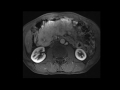

Large pancreatic neuroendocrine tumor

MRI and CT images demonstrate a large hypervascular mass in the pancreas, characteristic of a neuroendocrine tumor, with multiple hypervascular liver metastases.